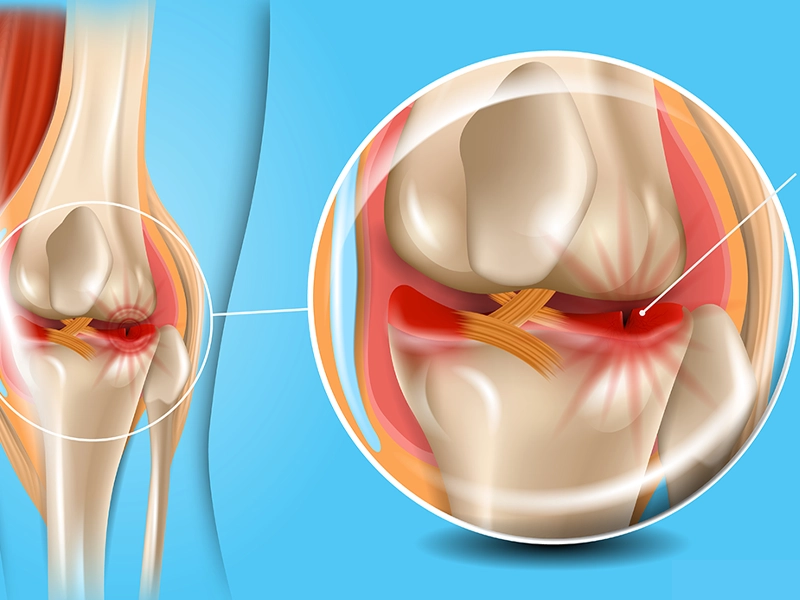

درد و التهاب در زانو ممکن است به دلایل مختلفی ایجاد شود، اما دو مورد از مهمترین آنها، روماتیسم مفصلی زانو و نقرس زانو هستند. این دو بیماری، گرچه هردو باعث درد، ورم و ناراحتی در ناحیه زانو میشوند، اما در واقعیت، تفاوتهای بسیار مهمی در علت، علائم، سیر بیماری و درمان دارند. در این […]